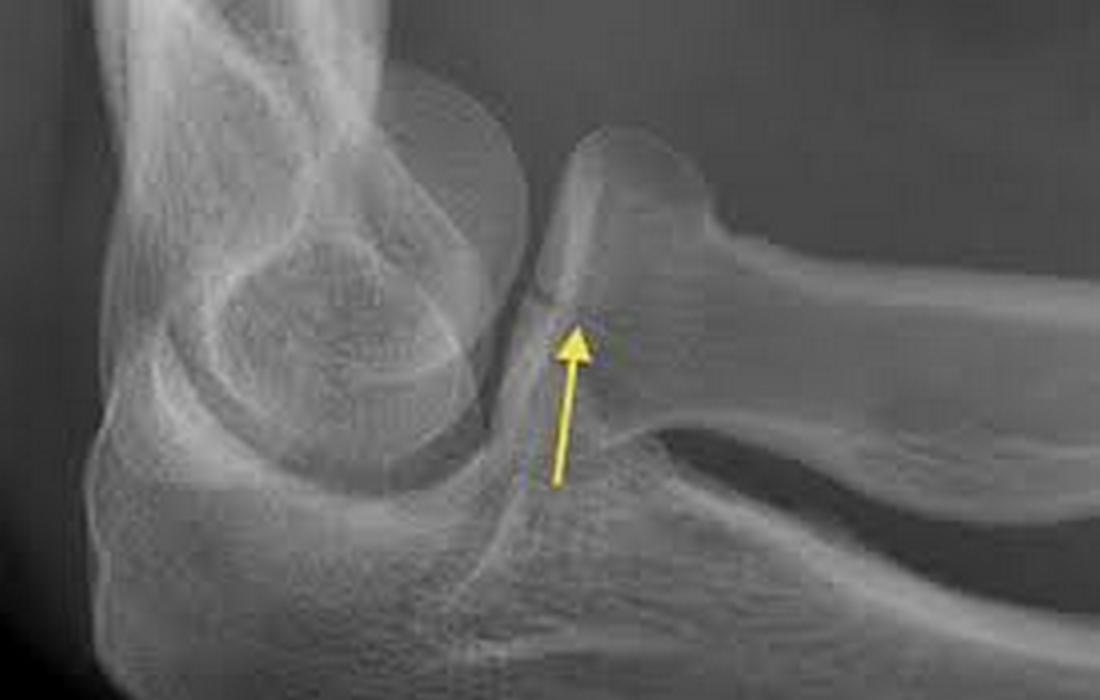

Κάταγμα Κεφαλής Κερκίδας

Η κεφαλή της κερκίδας βρίσκεται στην έξω πλευρά του αγκώνα και βοηθά στην κίνηση στροφής του αντιβραχίου.

Αίτια: συνήθως προκαλείται από πτώση στο τεντωμένο χέρι.

Συμπτώματα: πόνος στην έξω πλευρά του αγκώνα, δυσκολία στη στροφή του χεριού, πρήξιμο.